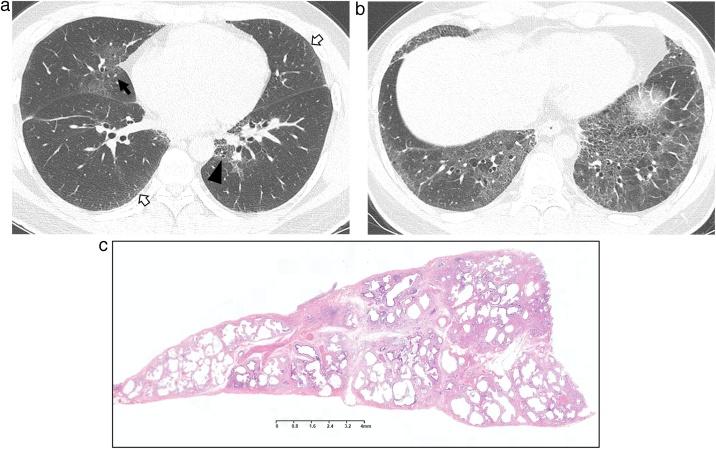

Interstitial lung abnormality (ILA) and nonspecific interstitial pneumonia (NSIP).

This review article aims to address mysteries existing between Interstitial Lung Abnormality (ILA) and Nonspecific Interstitial Pneumonia (NSIP). The concept and definition of ILA are based upon CT scans from multiple large-scale cohort studies, whereas the concept and definition of NSIP originally derived from pathology with evolution to multi-disciplinary diagnosis. NSIP is the diagnosis as Interstitial Lung Disease (ILD) with clinical significance, whereas only a part of subjects with ILA have clinically significant ILD. Eventually, both ILA and NSIP must be understood in the context of chronic fibrosing ILD and progressive ILD, which remains to be further investigated.